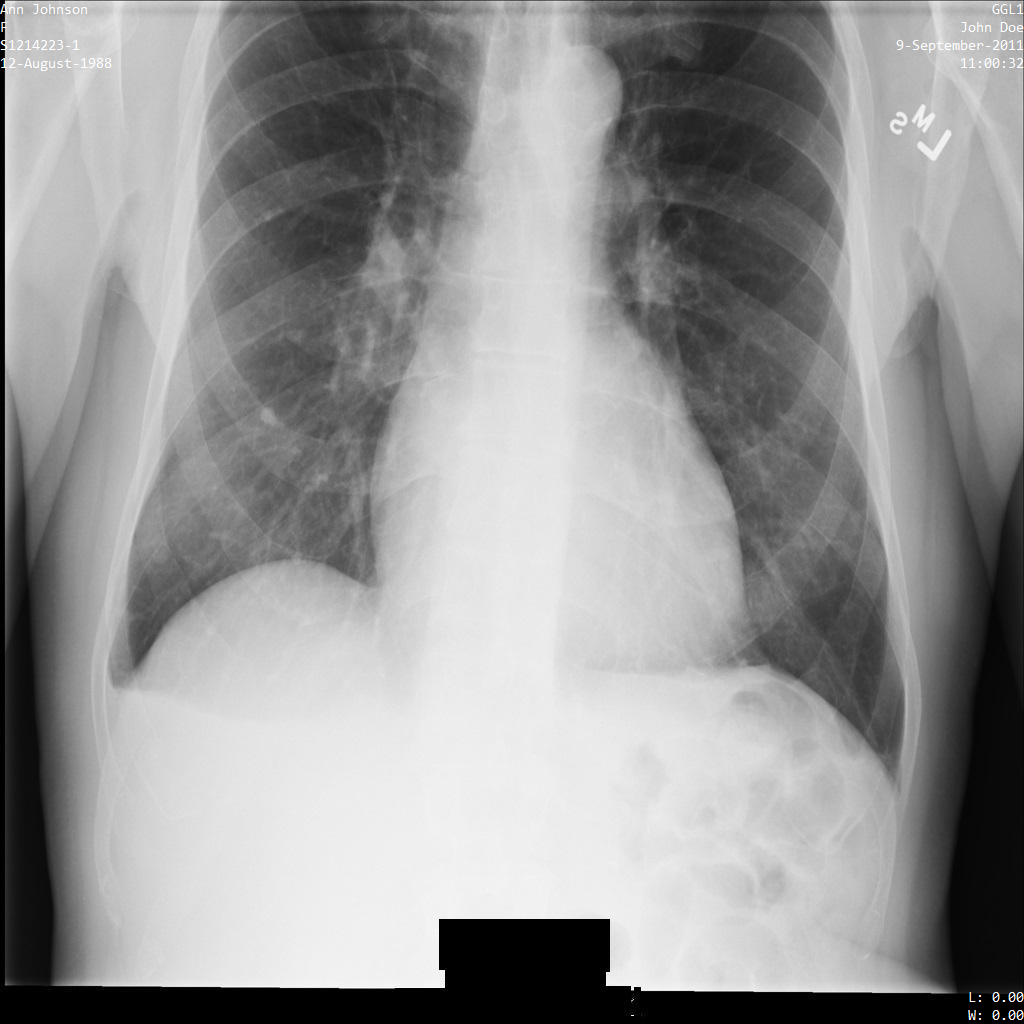

Chacune des sections suivantes fournit des exemples d'anonymisation de données DICOM à l'aide de différentes méthodes. Une sortie de l'image anonymisée est fournie avec chaque échantillon. Chaque exemple utilise l'image d'origine suivante comme entrée :

Vous pouvez comparer l'image de sortie de chaque opération d'anonymisation à cette image d'origine pour voir les effets de l'opération.

Une fois l'image envoyée à l'API Cloud Healthcare, elle apparaît comme suit. Alors que les métadonnées affichées dans les angles supérieurs de l'image ont été masquées, les informations de santé protégées qui sont incluses dans l'angle inférieur de l'image sont conservées. Pour supprimer également le texte incrusté, consultez la section Masquer le texte incrusté dans les images.

Une fois l'image envoyée à l'API Cloud Healthcare, elle apparaît comme suit. À l'exception des balises fournies dans la liste de suppression, seul PatientBirthDate est supprimé dans l'image, car il s'agit de la seule balise de la liste de suppressions qui correspond aux métadonnées visibles dans l'image.

Bien que le PatientBirthDate dans l'angle supérieur de l'image ait été masqué conformément à la configuration de la liste removelist, les données de santé protégées incrustées en bas de l'image sont conservées. Pour supprimer également le texte incrusté, consultez la section Masquer le texte incrusté dans les images.

Une fois envoyée à l'API Cloud Healthcare à l'aide du profil de filtre de tag ATTRIBUTE_CONFIDENTIALITY_BASIC_PROFILE, l'image apparaît comme suit. Les métadonnées affichées dans les angles supérieurs de l'image ont été masquées, mais les données de santé incrustées en bas de l'image reste affichées.

Pour supprimer également le texte incrusté, consultez la section Masquer le texte incrusté dans les images.

Une fois l'image envoyée à l'API Cloud Healthcare à l'aide de l'option REDACT_ALL_TEXT, elle apparaît comme suit : Bien que le texte incrusté au bas de l'image ait été supprimé, les métadonnées figurant dans les angles supérieurs de l'image sont conservées. Pour supprimer également les métadonnées, consultez la section Anonymiser des tags DICOM.